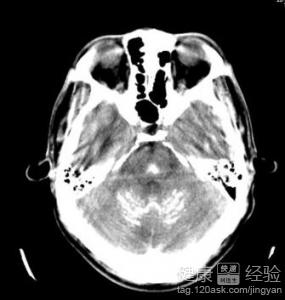

腦缺氧就可能會出現頭痛,頭暈,思維有些遲鈍,沒有太大的體力,反應非常地慢等.而新生兒出現腦缺氧的話就是新生兒缺氧缺血性腦病.是新生兒由於不同的原因而導致的腦部的血流量減少,缺氧等對新生兒的腦部造成的損傷.是兒童的神經系統最常見的一種傷殘原因,可以引發很嚴重的並發症,比如新生兒窒息,腦性癱瘓,癫痫,智力低下和視力障礙等.

1新生兒出現缺氧缺血性腦病的時候,病情的輕重是不一樣的,最主要的表現就是肌肉的張力下降,意識出現障礙,呼吸衰竭等.如果是重度患者的話就會出現前囟隆起,呼吸暫停不規則,呼吸衰竭,還有可能會致死.